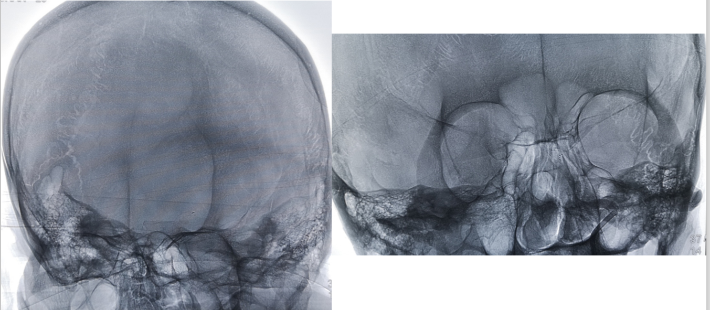

此次入院后,即予行全脑血管造影术,示左侧颈内动脉虹吸段重度狭窄。予患者家属充分沟通后,进一步行左侧颈内动脉虹吸段狭窄球囊扩张+支架植入术。

DSA

考虑狭窄段为夹层样改变,多角度导引导管造影,以更清晰地区分真假腔,选择最佳工作角度

--DSA显示左侧颈内虹吸段狭窄约72%。前交通开放,右侧大脑前动脉通过前交通动脉向左侧大脑前动脉、大脑中动脉供血区有代偿供血。